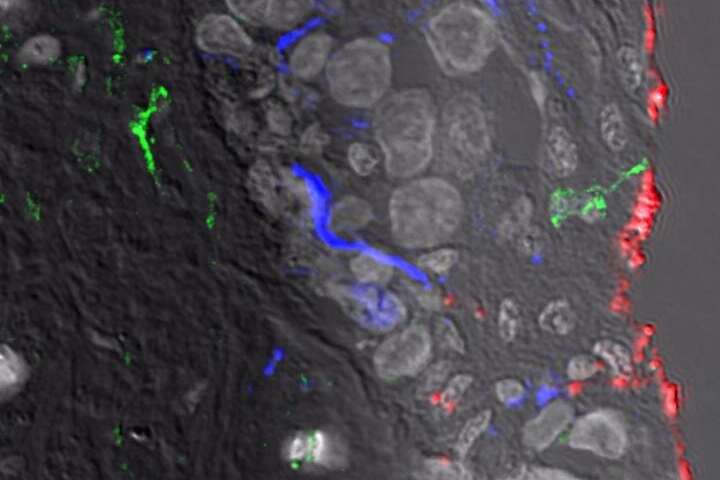

Specialised nerve endings & cells related to sexual function

Medical scientists and pathologist have been able to identify a number of highly specialised nerve endings and specialised cells related to sexual function. It is proposed that these nerve endings help with maintaining stimulation and erection. It is commonly reported by circumcised men (being circumcised an adult) that they find it difficult to maintain stimulation and an erection compared to previous experience with a foreskin. The loss of the foreskin results in a very significant loss of nerve endings which has been shown to significantly reduce the perception of sensitivity during sexual activity.